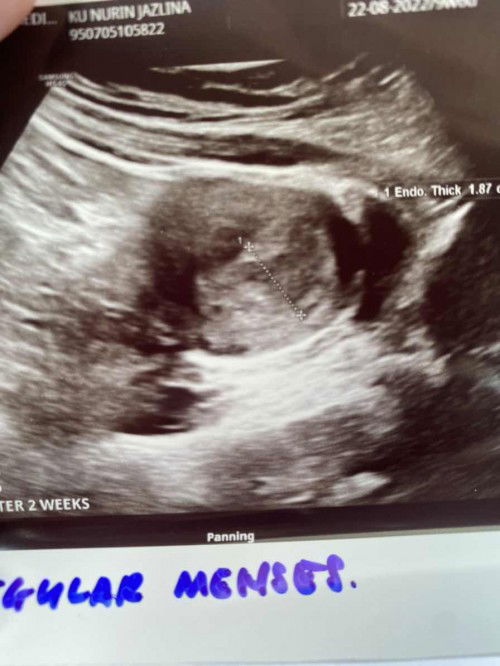

Dinding rahim tebal

Hi salam semua. Tadi saya buat ultrasound tp yg ada hanya dinding rahim tebal shj. Belum nampak apa2 lg. Last test upt last friday naik double line yg terang sikit dari sblm ni. Pakai cb digital dia tulis situ 2-3.. doctor ckp possibility pregnant sebab +ve and rahim tebal tanda kembang. So sy kena repeat after 2 weeks. adakah benda tu normal?

Hi. Last period 22 august, last check upt +ve adalah last jumaat. Tp bila scan dinding rahim menebal repeat after 2 weeks. Tp sonography ckp alhamdulillah takda pregnancy ectopic atau seakan dgn dia kalau tak dia dpt detect awal. Ada siapa2 mcm saya? Risau juga sebab pernah gugur bulan 5 tahun no.